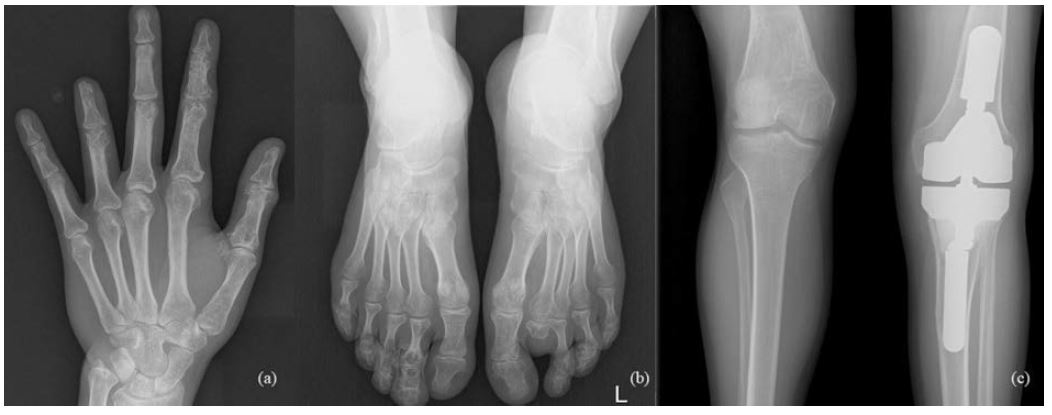

The 33-year-old man is actively treated and followed-up in HLUHS for Ollier disease for 3 years. Patient was followed-up by a pediatric orthopedic surgeon during his childhood. Due to adequate well-being patient did not seek medical attention for years. In 2017, he consulted an orthopedic oncologist complaining of formations and pain in the left hand. Performed studies showed these changes (Fig. 4): multiple enchondromas in the left hand, about 15 enchondroma foci in all phalanges in fingers I-IV and in metacarpal bones I-IV, about 10 enchondroma foci in toes I-V and metatarsals in the left foot, enchondroma in the proximal part of left tibia. The patient is followed-up every 3 months. In 2018 growth of the distal phalanx of the IV finger was observed – surgery was performed due to suspected malignancy, amputation of the distal phalanx of IV finger was performed (chondrosarcoma G2 was confirmed), curettage of the II finger enchondroma with cancellous bone grafting. The patient was hospitalized 4 more times in 1 year – 12 left hand enchondroma curettages were performed, most of which were performed with cancellous bone grafting. The left foot was operated 4 times – II toe amputation and 3 curettages with cancellous bone grafting, the enchondroma curettage with cancellous bone grafting of tibia’s proximal part. In 2 years (2018–2019), the patient was hospitalized 7 times, during which a total of 21 surgeries in different locations of bone were performed to protect from pathological fractures (Fig. 5). In February 2019, he underwent surgery for a reoccurrence in the proximal part of the left tibia – curettage with cancellous bone grafting and cementoplasties. Histology showed chondrosarcoma G2. Full body CT was done followed by a PET scan. Patient was followed-up. In studies performed in October 2019, recurrence of the disease was observed, and a special prosthesis was ordered. Extensive tumor resection according to ESMO guidelines [9] and left knee replacement surgery were performed. At present, there is no data on relapse, and the patient is monitored by orthopedic traumatologists and oncologists every 3 months according to the ESMO Clinical Practice Guidelines for diagnosis, treatment, and follow-up [9]. The patient is walking at bearing full weight, worked, knee flexion is up to 80 degrees.